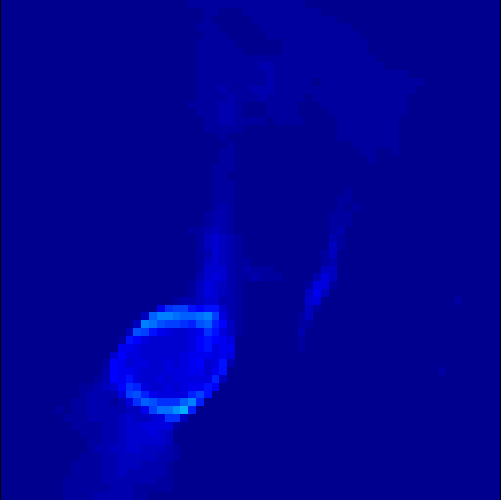

The first data set consists of a heart-shaped region and three circles on a static background (see figure 1 (a)). The two smaller circles are assumed to belong to the same tissue type and therefore to the same subregion, which causes a total of four subregions, including the background. To simulate a more realistic application of dynamic SPECT imaging, we used a synthesized representation of a rat liver as a second data set (see figure 1 (b)). The temporal concentration curves used to simulate the data sets are shown in figure 2. As before, the total number of subregions was chosen to be equal to four in order to provide a both simple and realistic shape model.

Figure 1: Phantoms of the tested data sets

Figure 2: Temporal concentration curves in all subregions. (a) Region 1 corresponds to the circle which is partly behind the heart, region 2 are the two outer circles and region 3 is the heart. (b) Region 1 represents the outer tissue in the phantom, region 2 the ring-shaped region of the liver and region 3 the inner of region 2.